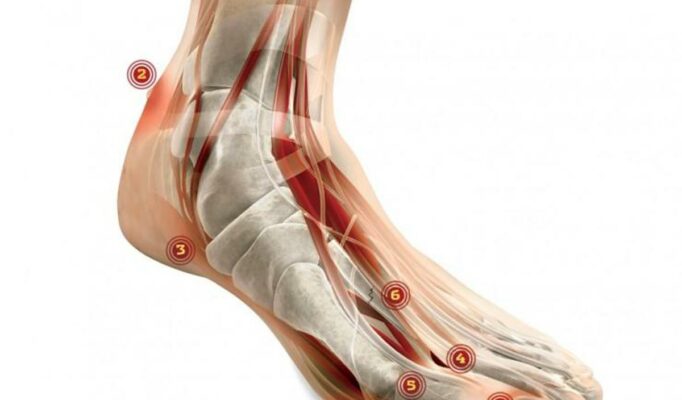

Metatarsalgia Mortona jest chorobą stóp powodującą przeszywający ból śródstopia, zwłaszcza podczas długiego stania, chodzenia i biegania. Przyglądając się bliżej tej chorobie, należy pamiętać, że głowy wszystkich pięciu kości śródstopia łączą więzadła, zwłaszcza więzadło poprzeczne wzmacniające sklepienie poprzeczne stopy. Pod nim natomiast przechodzą nerwy podeszwowe, które unerwiają stopę, a najważniejszym z nich jest nerw podeszwowy wspólny palców. Ból pojawiający się przy metatarsalgii Mortona jest wynikiem ucisku tegoż nerwu podeszwowego przez więzadło poprzeczne, jego nadmiernego rozciągnięcia czy powstania stanu zapalnego. Poza dokuczającym, utrudniającym normalne funkcjonowanie bólem, wynikiem choroby są zmiany zwyrodnieniowe w okolicy kości śródstopia.

Do ucisku więzadła poprzecznego na nerw podeszwowy wspólny palców dochodzi między innymi wskutek przeciążenia stopy, wywołanego długim staniem, bieganiem czy skakaniem, jeżeli użytkownik ma źle dopasowane obuwie. Samo schorzenie częściej dotyka kobiety niż mężczyzn. Najbardziej narażone są kobiety po 50. roku życia, ale także osoby o wysokim podbiciu, otyłe i zmagające się z płaskostopiem poprzecznym. Inne czynniki ryzyka to: wąskie przodostopie, stopa wydrążona, palce młotkowate i młoteczkowate, paluch koślawy czy uraz tej okolicy stopy. W końcu nerwiak Mortona może być wynikiem schorzenia, które dotyka bezpośrednią okolicę nerwu podeszwowego (tłuszczak, ganglion, zapalenie kaletek maziowych, zapalenie torebek, zapalenie stawów śródstopno-palcowych).

Najczęstszym objawem, który wskazywać może na stopę Mortona, jest ból zlokalizowany na wysokości głów kości śródstopia, od strony podeszwowej i blisko palców, najczęściej między II i III oraz III i IV palcem stopy. Pierwszym objawem jest jednak mrowienie, choć nikt nie bierze tych objawów na poważnie.